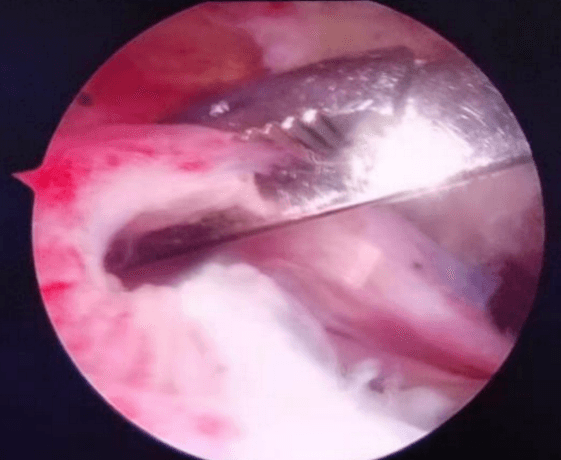

七年前從零出發,從無到有,從有到精,李鵬主任帶領團隊人員,先后在西安、上海、北京、廣州等獨家頂級關節運動醫學中心學習,屢次開創引進新技術,填補我院多項技術空白。先后開展了首例膝關節鏡、首例肩關節鏡手術,首例踝關節鏡手術,首例肘關節鏡手術,首例髖關節鏡手術,完成了技術要求高、難度大的肩袖損傷修復手術、肩關節復發性脫位、BanKart損傷修復手術,后交叉韌帶下止點骨折、膝關節多發韌帶損傷重建手術等,標志著我院在骨關節運動醫學專業及關節鏡微創手術技術的顯著提升。

當前越來越多的人意識到健康的身體是1,其他的都是0,有了這個1,其他的0才有了存在的意義和價值。所以越來越多的人開始關注運動、開始參與運動。然而,如何正確的運動,如何預防運動損傷,如何在運動損傷后得到專業的治療,如何在運動損傷治療后得到快速的康復等,就需要一個專業的學科來解決這些問題。這個學科就是運動醫學。運動醫學是一門新興的醫學科目,是醫學與關節運動相結合的綜合性應用科學。主要是研究與關節運動有關的醫學問題,包括關節的慢性勞損和急慢性損傷。范圍涵蓋了膝關節、肩關節、髖關節、踝關節及肘關節。膝關節骨關節炎、半月板損傷、交叉韌帶損傷、髕骨脫位、游離體(滑膜軟骨瘤病)、肩關節凍結肩、肩袖損傷、肩峰撞擊征、肩關節復發性脫位、肩關節SLAP損傷、肘關節骨關節炎、踝關節撞擊癥、踝關節不穩以及臀肌攣縮癥、髖股撞擊癥等,這些疾病都可以到運動醫學科就診。運動醫學能夠有效的、針對性的解決各類急慢性關節疼痛。主要是利用關節鏡微創技術,能夠快速有效的緩解關節疼痛,具有創傷小、恢復快、效果顯著等優點。

微創、精準、快速康復已成為骨科疾病與創傷治療的必然趨勢。我院骨關節及運動醫學亞專科是我院外科病院重點發展的亞專科方向。李鵬作為專業團隊的負責人,科室目前配備有全套進口關節鏡手術設備,高清顯像系統,全體醫護團結協作,嚴謹細致,踏實前行,以精湛的醫療技術和優質的護理服務,為患者提供了優質醫療服務,贏得了廣大患者的信任和肯定。

肩袖損傷手術

擅長治療各種骨關節外傷、骨關節疾病。手術方面擅長髖、膝關節置換術、膝關節單髁置換術、脛骨高位截骨術、股骨頸骨折及轉子間骨折等手術。富血小板血漿(PRP)治療骨關節炎。擅長關節鏡下膝關節交叉韌帶重建、半月板損傷縫合、髕骨脫位、肩袖修補,肩峰撞擊征、鈣化性肌腱炎,肱二頭肌長頭腱炎,髖關節盂唇損傷、髖關節撞擊征、踝關節不穩、踝關節韌帶損傷、肩關節不穩、肩周炎、各類關節內骨折、關節脫位的手術治療。